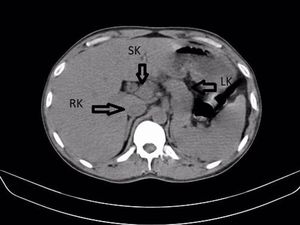

Seorang pria di India terkejut menemukan ginjal ketiga saat dirawat karena infeksi saluran kemih. Kondisi langka ini memicu masalah kesehatan yang serius.